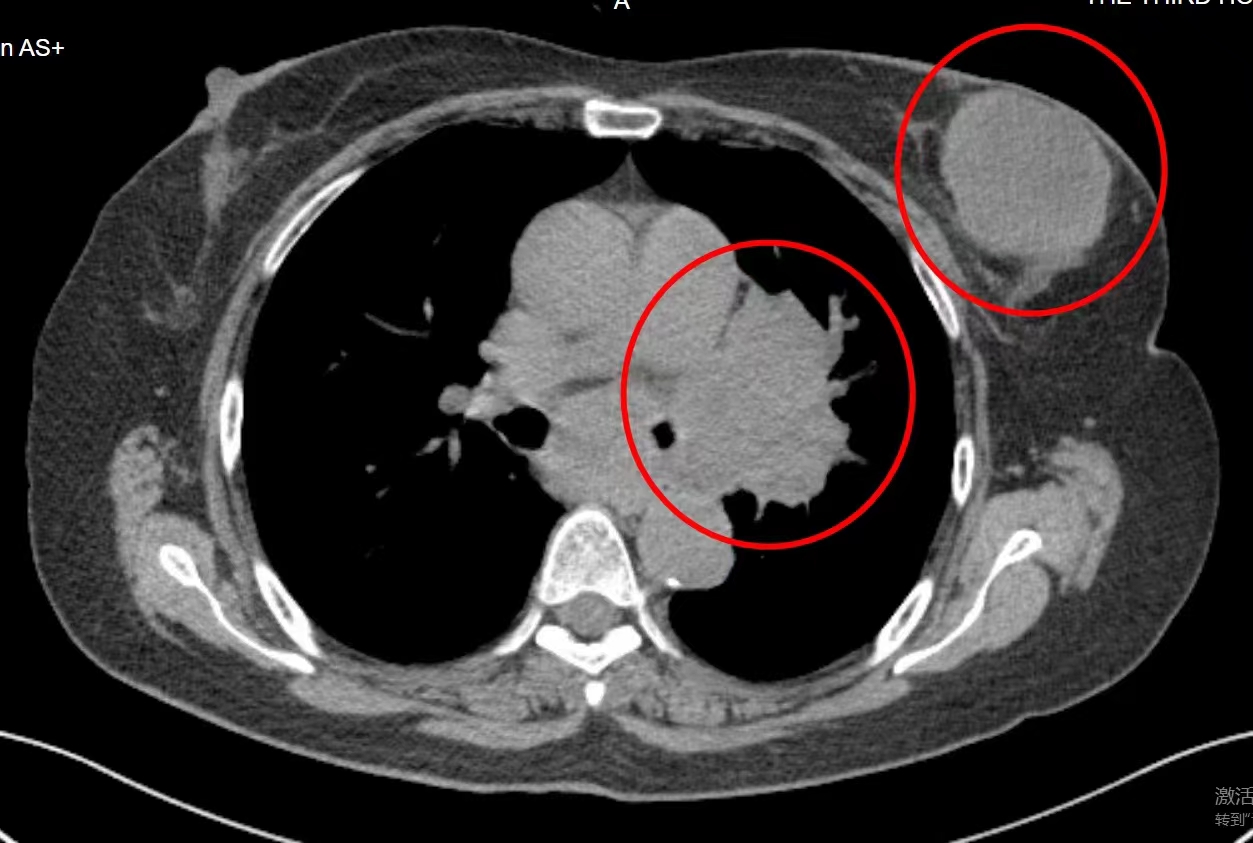

在中医辨证论治的配合下,张女士的治疗顺利完成,无明显不适。治疗结束后,张女士再次来到广药三院肿瘤科一区进行复查复诊,这次的检查结果显示,张女士肿瘤缩小至2公分,临床症状消失,疗效评价CR

没有想到自己能在这么轻松的状态下完成治疗,张女士对彭主任说:“这个治疗方法好,没有痛苦,恢复也快,做完治疗回家也能正常工作正常生活,心理也没这么大负担了。”医生表示,创伤小、副作用低正是肿瘤微创治疗技术特点,再结合中医药进行调理巩固,能大限度地帮助患者恢复身体,增强免疫力,提高对癌症的抵抗力。